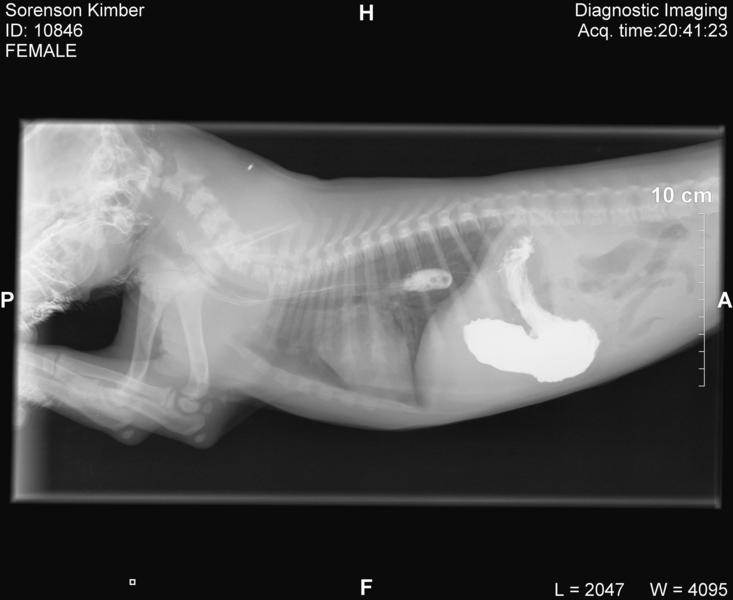

Kimber's trip to emergency

• Click to enlarge image Sorenson Kimber Jordan_CR_20090125_202123_6.jpg

If you look by her front sholder you can see her microchip implant.  Pretty cool hey!